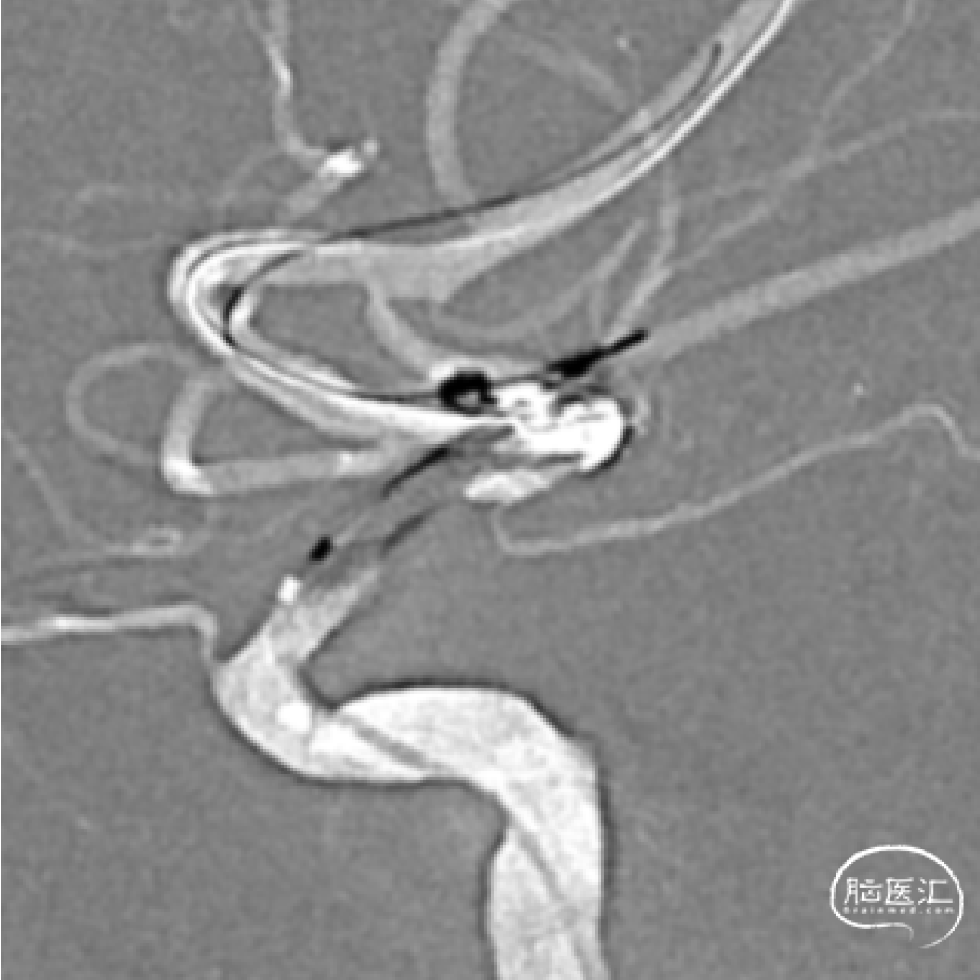

➢DSA(2023.11.10)

植入Atlas支架,动脉瘤不显示,狭窄改善。

术后正侧位。